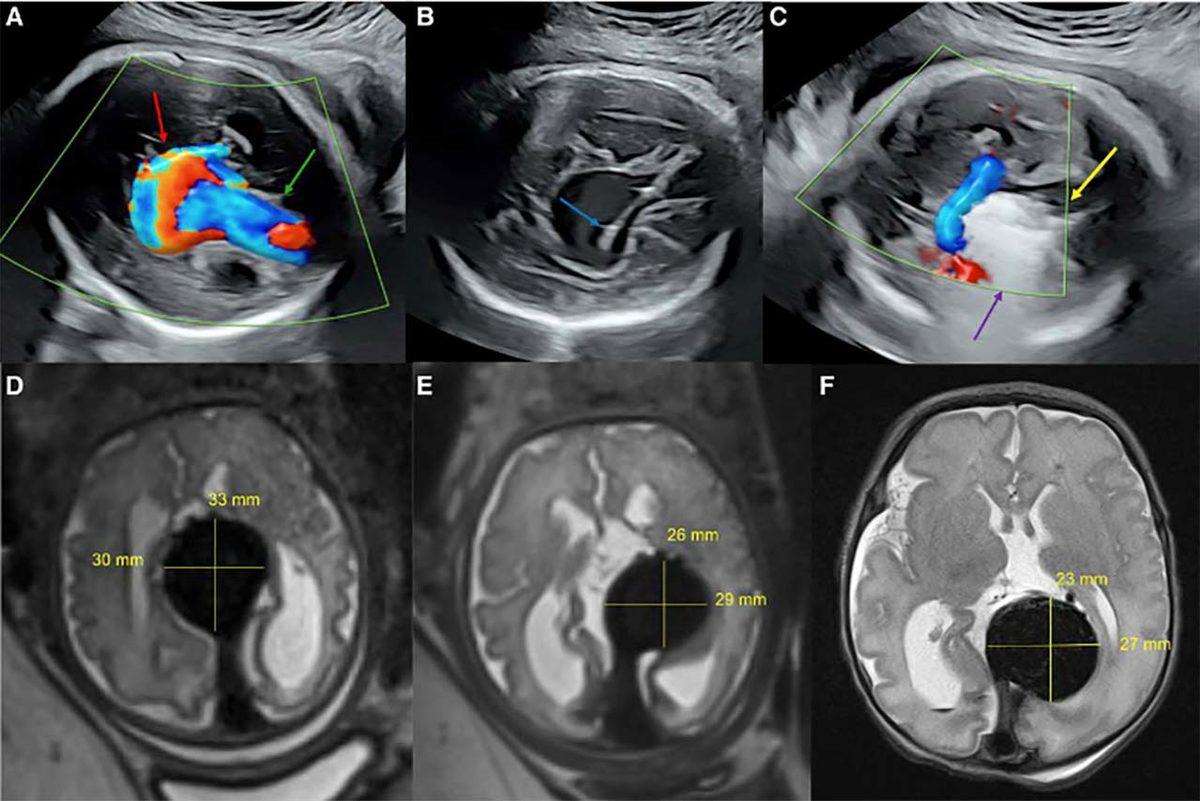

Yapılan incelemelerde fetüste Galen malformasyonuna sahip bir damar görüldü. Bu durum, beyindeki arterlerin, olması gerektiği gibi önce kılcal damarlardan geçmesi yerine doğrudan damarlara bağlanmasına neden oluyor, ölümcül sonuçlara yol açabiliyor.

Durumu ölümcül yapan şey de aslında kan basıncından kaynaklanıyor. Kılcal damarlar, kan basıncını yavaşlatma görevini üstlenirken malformasyon nedeniyle kanın doğrudan damarlara akması, aşırı yüksek tansiyona neden olabiliyor.

Bu durum neticesinde özellikle doğum ve doğumdan sonrasında beyin ve kalp, aşırı basınç altına giriyor. Bu basınç, pulmoner hipertansiyon, kalp yetmezliği ve diğer hayati durumlara yol açabiliyor.

Operasyon, ABD Gıda ve İlaç İdaresi’nin gözetiminde gerçekleşti. Cerrahlar, ultrasondan faydalanarak rahim ve fetüs içinde operasyon bölgesine ulaştı, fetüs beynindeki yüksek basınçlı kan damarlarını tıkayarak doğum sırasında oluşacak yüksek basıncın önüne geçti.